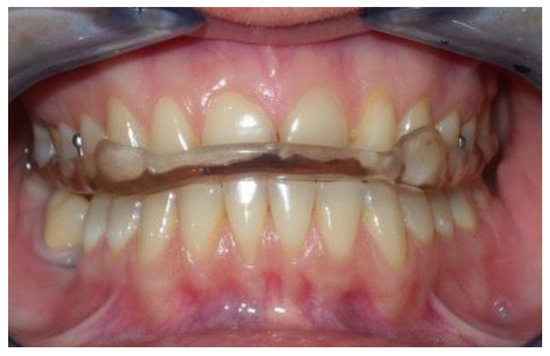

- A heat-cured acrylic resin upper plate (1),

- A heat-cured acrylic resin lower plate (2),

- An anterior hinge (3),

- Two vestibular springs made with orthodontic wire (4),

- Two or more Adams clasps and/or two ball clasps (5),

- A vestibular steel arch (6).